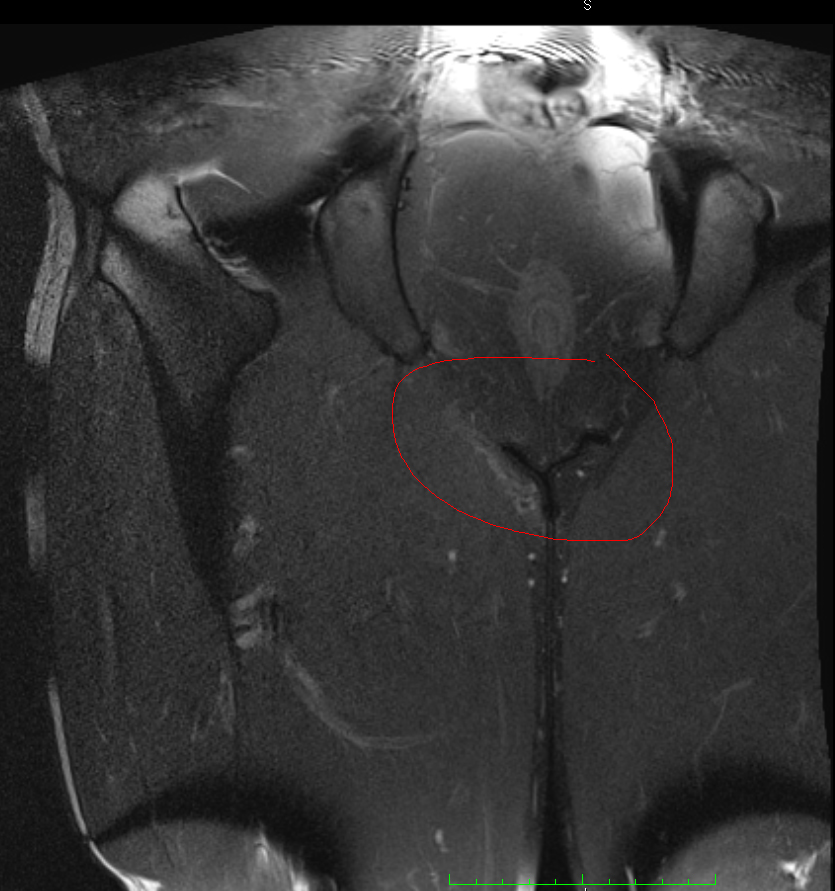

Nun habe ich mir die MRT-Bilder selber angeschaut und bin der festen Meinung, dass genau in dem Bereich wo ich Probleme habe, eine deutliche Auffälligkeit im Vergleich zum anderen Bein zu sehen ist. Diese hellere Struktur ist wohlgemerkt nicht nur in einer Schicht der Aufnahme zu sehen, sondern auf 14.

Kennt sich jemand mit MRT-Bildern aus und kann dazu was sagen? Ist dort eine Auffälligkeit zu sehen, oder ist das Zufall? Deutet dies auf eine Entzündung hin? (Ja ich gehe noch zum Arzt mit den Bildern)

Anbei einmal zwei Unterschiedliche Sequenzen. Das schwarze Y was ihr seht ist der Bereich linkes Bein/rechtes Bein, oben Genitalbereich. Links ist eine deutliche hellere Struktur zu erkennen als rechts (Adduktoren).